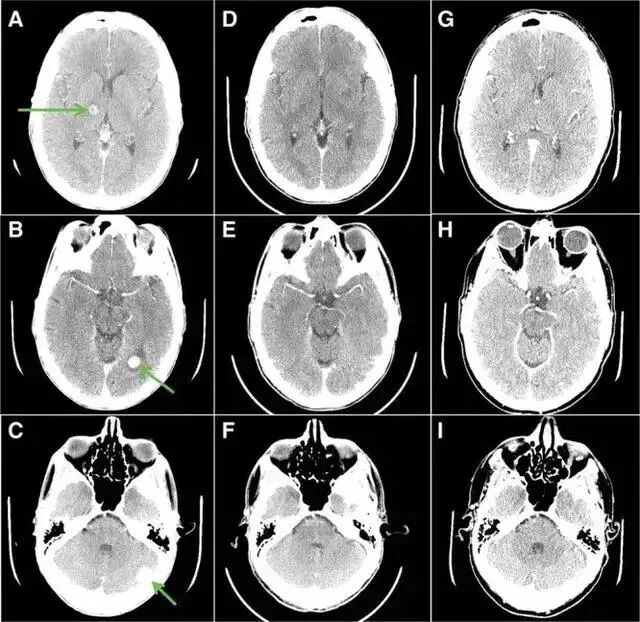

大叔每天以400 mg / ㎡口服,三周后,疼痛和呼吸困难症状消失,不在需要吸氧,并且,全身的肿瘤缩小46%,胸壁5公分的病灶已看不到摸不到!脑部肿瘤大部分消退;吃药5个月,症状不断改善,全身的肿瘤缩小77%,脑转移完全消失!!!

第26天(C,D)和第155天(E,F)胸部图像,肿瘤缩小77%!

吃药前箭头指的都是肿瘤,20几个,吃药26天(DF)大部分消失, 吃药155 天(GI)肿瘤完全消失!